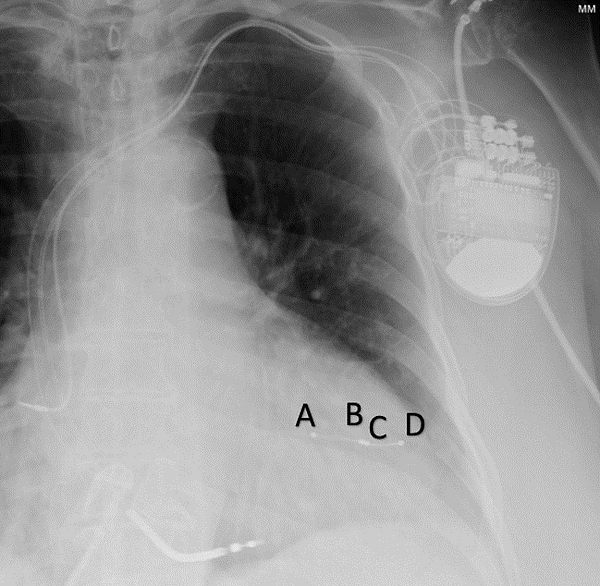

The information in figure 1 suggests which of the following

A probable lead dislodgment

B lead insulation failure

C patient going into acute CHF

D patient needs to reduce diuretics

Figure 1